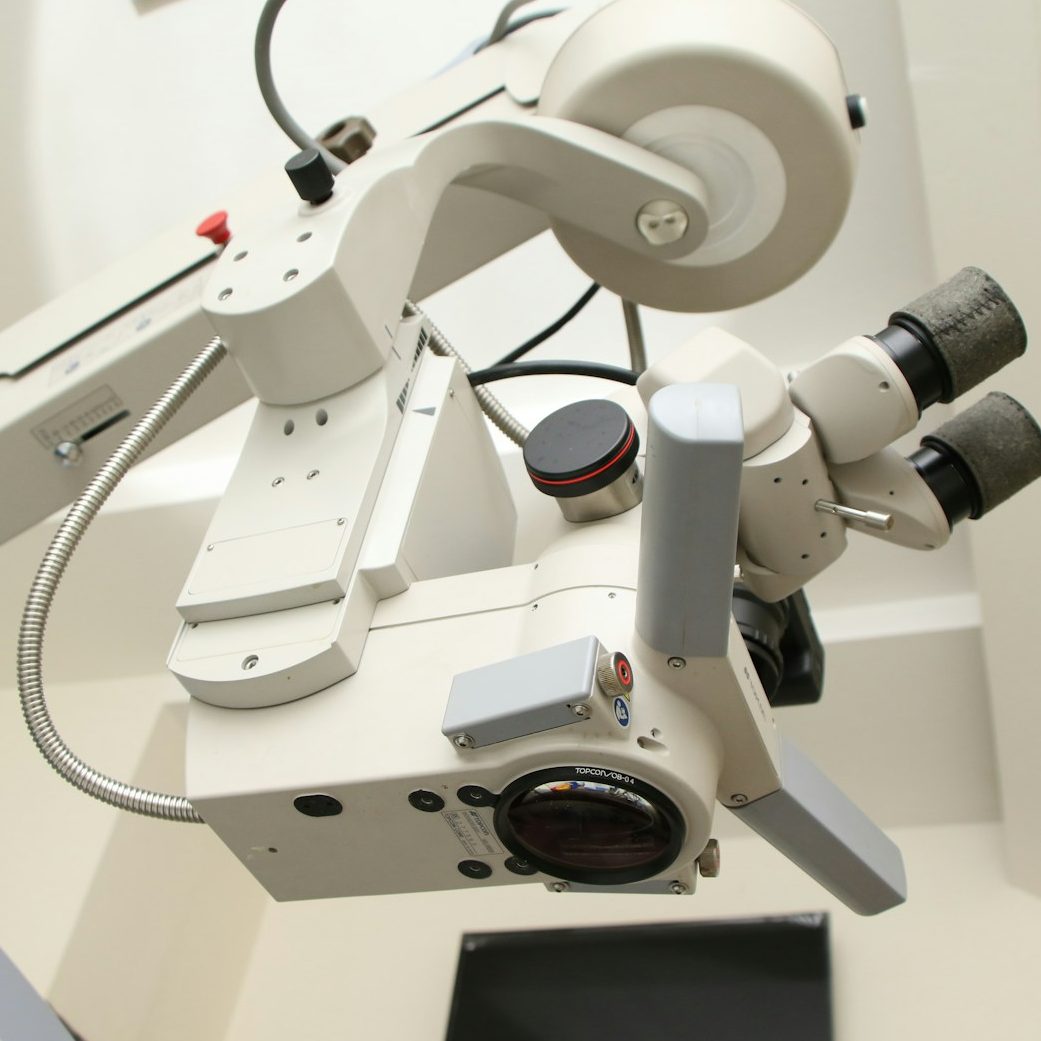

Soins de Haute Technicité

Traitement dentaire sous microscope opératoire